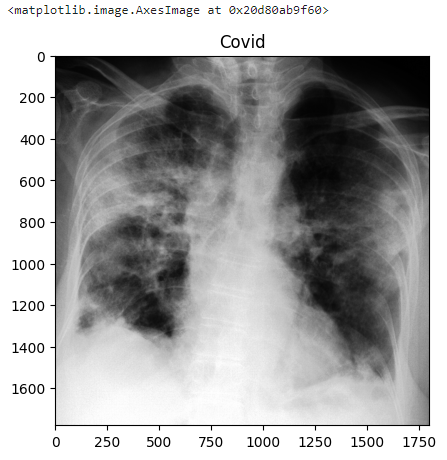

index = 100

plt.title(class_list[dset[index]["target"]])

plt.imshow(dset[index]["image"])